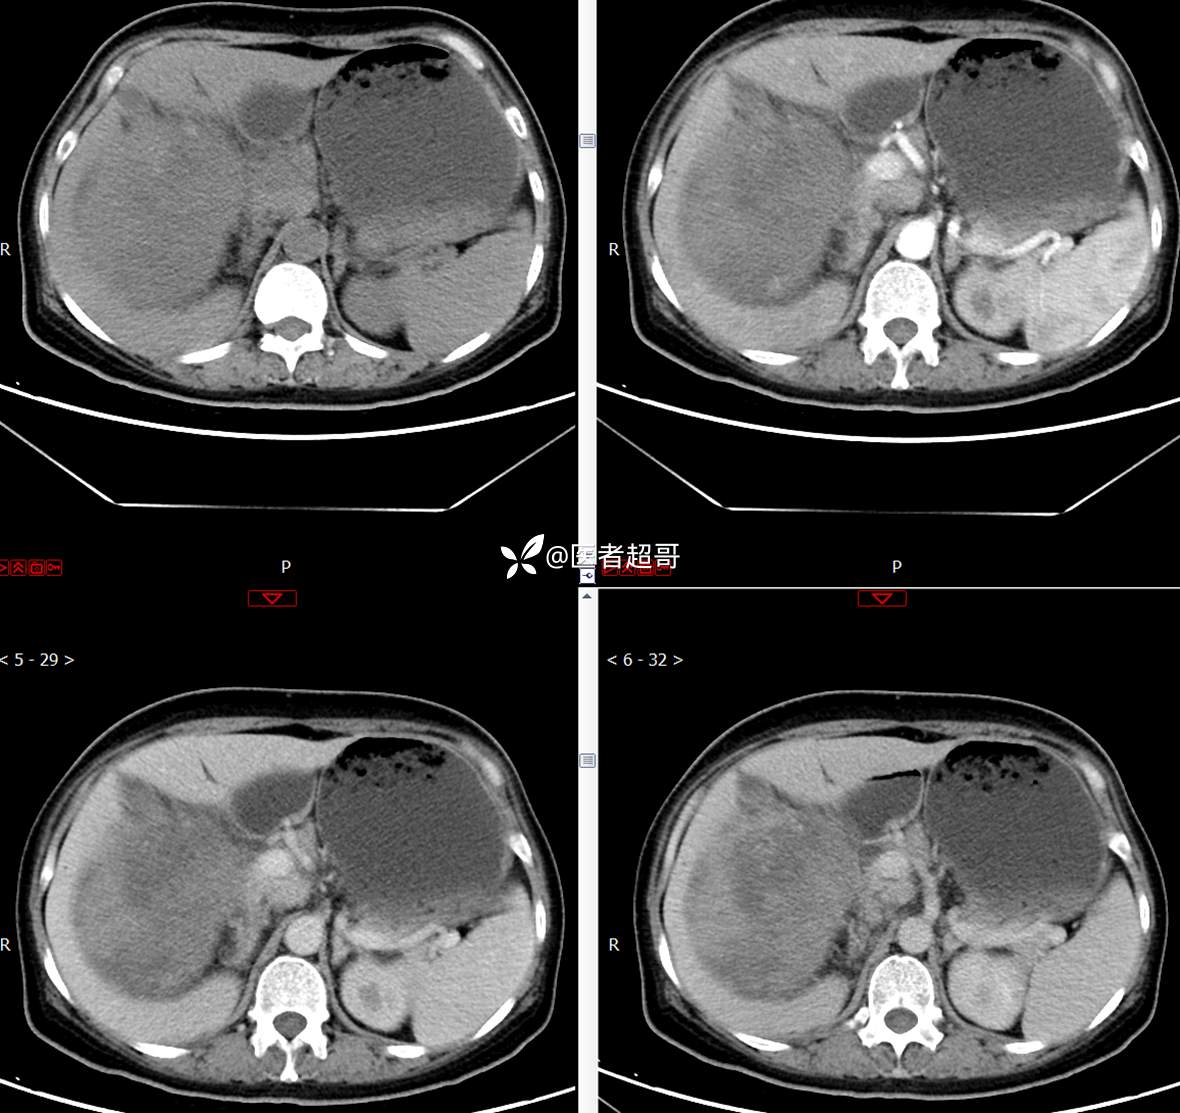

现病史:患者1周余前发现右上腹有一半球形巨大肿物,约18cm*15cm大小,既往贫血病史3年余,诉乏力,易疲劳,偶有头晕,活动后心悸,无腹痛、腹胀,无恶心、呕吐,无尿频、尿急、尿痛,无排尿困难,患者为求进一步治疗,来我院消化内科就诊,门诊行肝.胆.胰.脾.肾彩超示:右肾上部囊实性占位,范围约18.0cm×11.7cm×16.4cm,边界清,形态规则,建议进一步检查,腹膜后实性结节。我科遂以“肾肿物”收治入院,患者自发病以来,神志清、精神可,睡眠、饮食可,二便正常,体重、体力略有下降。